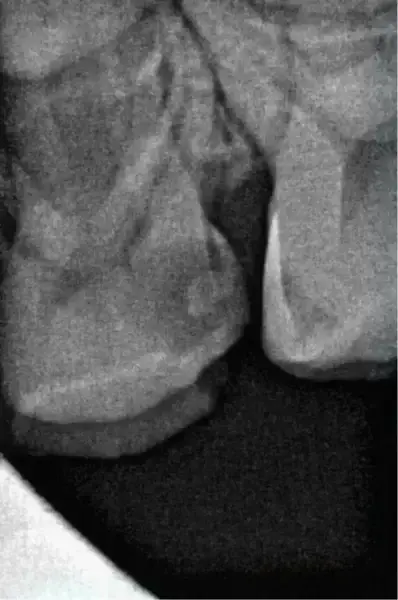

Начало на транса: след анестезия и поставяне на кофердам бяха използвани четири NiTi пили с ендодонтски мотор Jeni с интегриран апекслокатор. Първо бе приложен 25/.12 HyFlex EDM разширител на орифициумите (COLTENE), за да се подготви ендодонтският достъп и да се разшири коронарно. Не е задължително да се създава гладък път. Следващите три пили могат да следват естествения профил на канала по оптимален начин. Реалната обработка на каналите бе направена с пили 20/.05 HyFlex EDM и 25/~ HyFlex EDM OneFile (фиг. 3 и 4). По време на този процес предварително програмираният Jeni режим движи пилите постепенно в апикална посока. Щом се чуе звуков сигнал за иригация, инструментите се извеждат от канала, след което се въвеждат по-дълбоко отпреди. Тази процедура се повтаря, докато не се достигне почти до апекса. В конкретния случай пилите стигнаха до работна дължина още при първото въвеждане. За финал апикалната една трета бе обработена с пила 40/.04, която също бързо бе въведена до пълна работна дължина.

Като цяло засегнатият зъб бе обработен бързо и надеждно с помощта на напълно автономен копилот – истинска благословия, като се има предвид, че съдействието особено при (малки) боязливи пациенти е ключово, а то бива постигнато благодарение на редуцирано време за лечение и надежден работен протокол. Това в комбинация с предразполагаща децата, успокояваща среда елиминира голяма част от първоначалните тревоги дори при случаи на ендодонтско лечение. След обилна иригация на каналите с натриев хипохлорит и подсушаване със съответните подходящи хартиени щифтове каналите бяха изпълнени с калциев хидроксид, а коронката бе възстановена с керамична педиатрична коронка, която бе адхезивно залепена. След проверка на оклузията и артикулацията случаят бе приключен, а пациентът си тръгна доволен и без болка (фиг. 6).